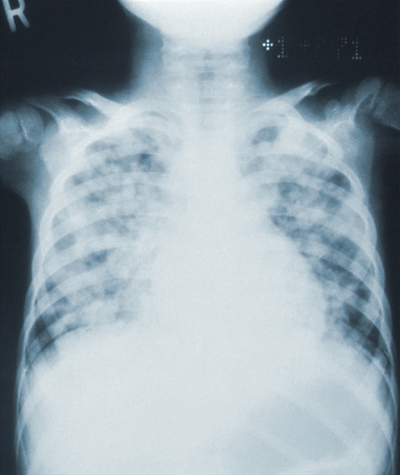

폐렴은 세균이나 바이러스에 의해 폐의 세기관지 이하 부위, 특히 폐포라 불리는 공기주머니에 발생한 염증을 말합니다. 폐의 정상적인 기능에 장애가 생겨서 발생하는 폐증상과 몸 전체에 걸친 전신적인 증상이 나타납니다.

폐렴이 발생하는 원인은 세균이나 바이러스, 혹은 곰팡이에 의한 감염으로 인한 미생물에 의한 감염과 화학물질이나 구토물 등 이물질의 흡인, 가스의 흡인, 방사선 치료 등에 의해 발생하는 비감염성 폐렴이 있습니다.